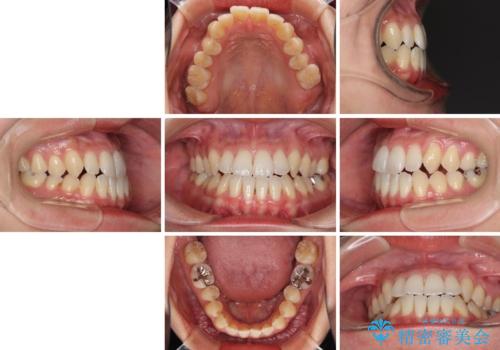

前歯のデコボコ インビザラインによる矯正治療

- 上下前歯の叢生と奥歯の反対咬合を気にして来院された患者様です。

インビザラインを用い、下顎はIPR(歯と歯の間を削る)と歯列全体を後方に移動させ、上顎は側方に拡大させることで歯列を改善していくこととしました。

骨格的に下顎が左側前方にずれているため、上下正中のズレや左右奥歯の咬み合わせを理想的な状態とすることは困難でした。